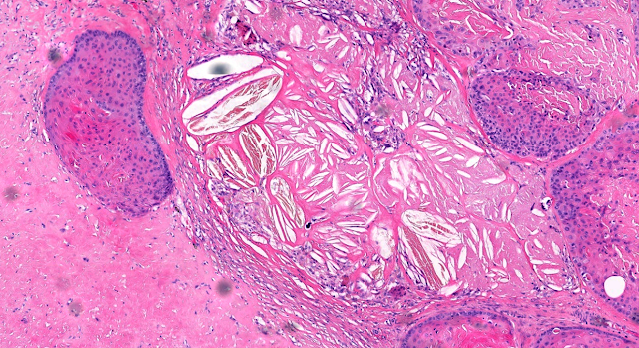

Dermatopathology Case 263 September 07, 2022 A 75 year old man with a skin lesion on the left side of the neck. Answer Read more